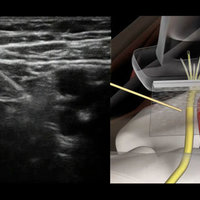

A unique system that combines live sonoanatomy via ultrasound scans, 3D animated anatomy and real time video of the performance of regional anaesthetic nerve blocks. All elements are combined and synchronised with audible narration.

* 3D Animated anatomical models, interlinked with live ultrasound scans.

* Synchronised (US and camera) nerve mapping scans.

* Annotated ultrasound screen shots.

A tab system gives the user access to anatomy, procedure, tips and equipment. The anatomy tab gives an overview of anatomy related to the specific block, it includes schematic diagram’s which can be expanded to full screen. The procedures tab is a full pictorial and text guide to the performance of the specific block, including annotated ultrasound screen captures to help visualise nerves. The tips tab contains useful advice related to the selected block, also included is advice on the use of ultrasound and local anaesthetics.